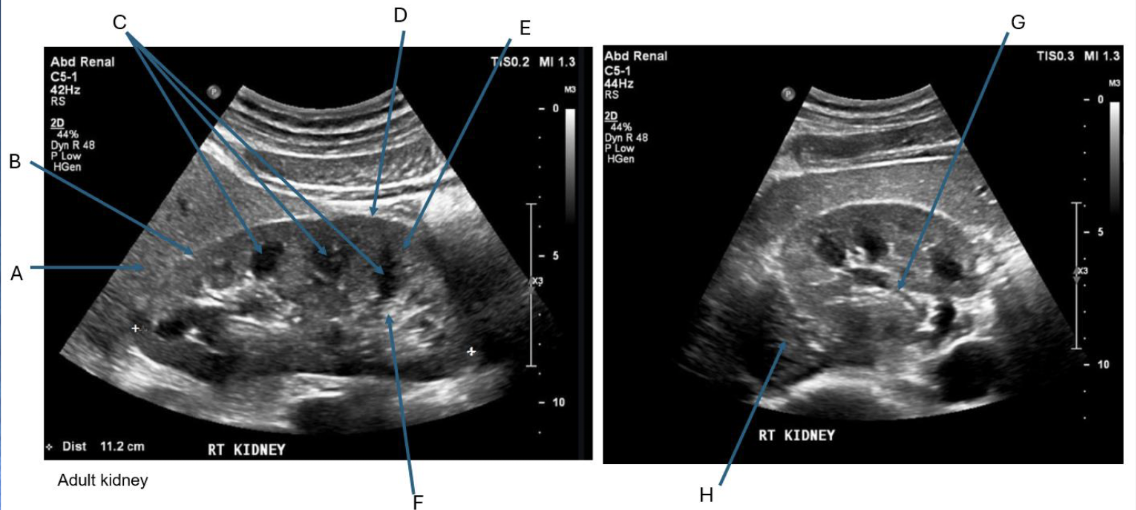

Label + Which is Long/TRV

Long then Trv